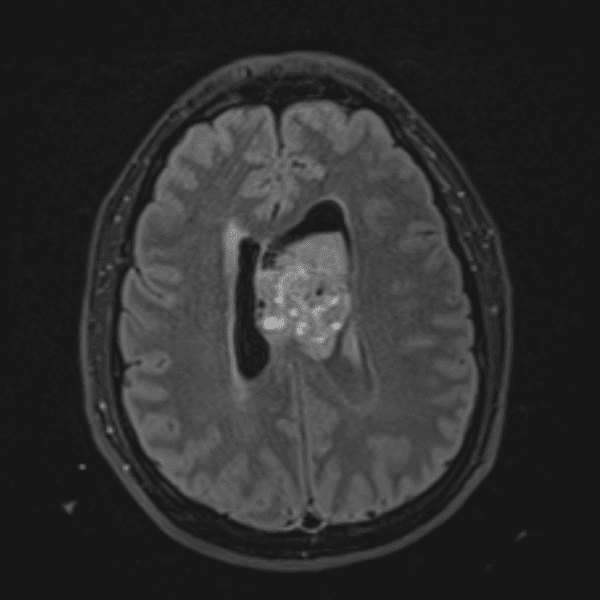

Classic Cases